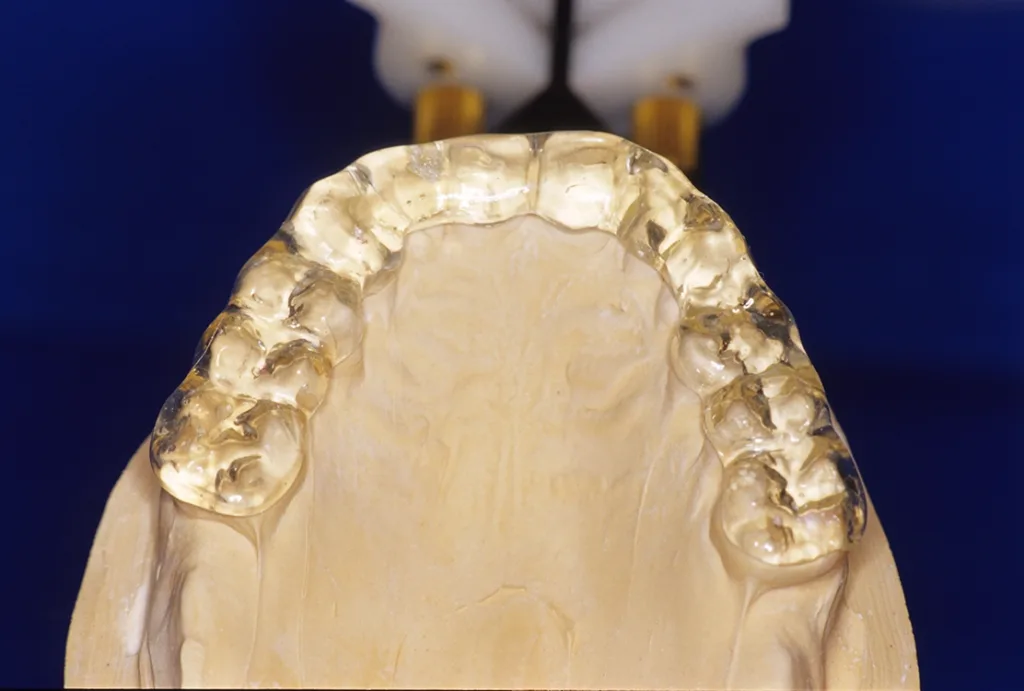

- Anfertigung einer Relaxierungsschiene im OK (bei Deck- oder Tiefbiss im UK) zur funktionellen Dekompensation mit frontalem Aufbiss und temporärer Entlastung im Molarenbereich durch vertikale Freistellung von 1 mm (GOZ 7000 ff.) (Abb. 5 bis 7).

Ziel ist die Dekompensation gewohnheitsbedingter Fehlfunktionen zur Entlastung, Revaskularisierung und Mineralisation des Alveolarknochens vor Implantation. Nach Durchführung der genannten Maßnahmen erfolgt bereits nach einer Tragezeit von vier bis sechs Wochen eine Entlastung von habituellen Gebrauchsmustern. Aus Hygiene- und Stabilitätsgründen werden die Schienen als Streuschienen in einer Stärke von ca. 1,5 mm gefertigt. Sie reichen jeweils bis zum Sechsjahrmolaren (Abb. 8).